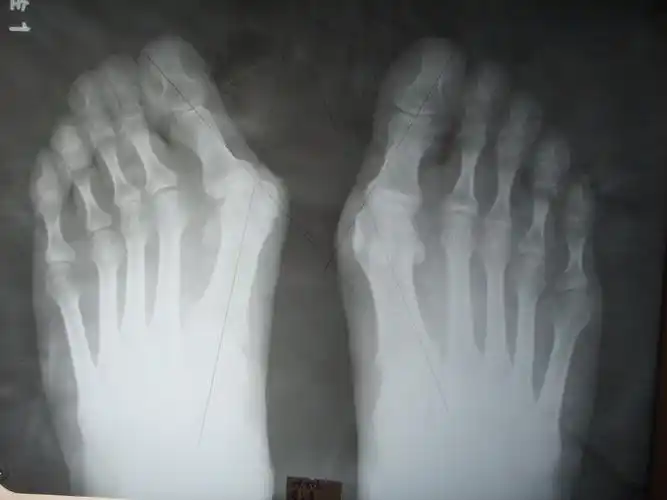

36岁双足拇外翻畸形矫正手术一例

负重x线片观察:第一二跖骨间夹角增大明显,第二跖趾关节半脱位.